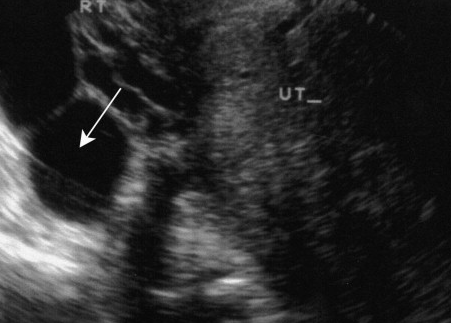

Pyosalpinx is often diagnosed in several ways, such as by swabbing, getting a blood test to check for infection, imaging, or even surgery. The doctor sometimes uses a CT scan, an MRI of the pelvis, or an ultrasound of the pelvis for the diagnosis. On the other hand, if the fallopian tubes are wide open, the fluid will flow into the pelvic cavity directly from the tube openings. A hydrosalpinx is diagnosed by a doctor if the tubes are plugged and fluid cannot drain.